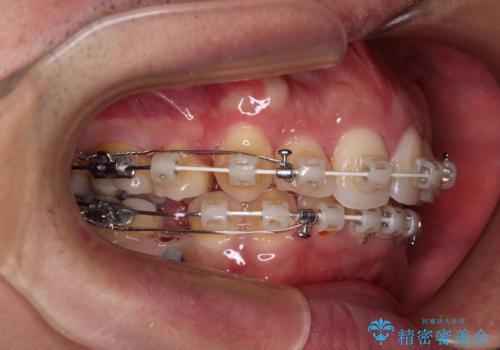

- 矯正装置

- 審美装置

上顎歯列幅を側方に拡大するとともに、歯列全体を後方に移動させるためのアンカースクリューと補助装置を使用し、上顎左右第一小臼歯2本、下顎左右第二小臼歯2本、計4本を抜歯し、ワイヤー装置にて矯正治療を行うこととしました。